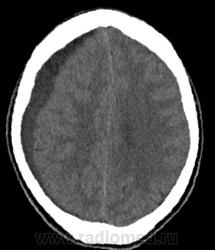

Динамика отчетливо положительная, субдуральное гнойное содержимое практически полностью эвакуировано. Дислокация срединных структур уменьшилась. Определяется постоперационная пневмоцефалия.

Пациент провел 6 суток в реанимации. Состояние стабилизировалось. На 9е сутки пребывания очередное контрольное КТ:

В конвекситальных отделах правой теменной доли появилось несколько гиподенсных локальных зон, плотностью +15+20HU, с четкими неровными контурами; аналогичные зоны в полюсе правой лобной доли +19+25HU и в полюсе правой височной доли - формирующиеся кистозно-атрофические изменения? Сохраняется смещение срединных структур влево на 4мм. В зоне операции (КПТЧ) установлен дренаж, определяются немногочисленные пузырьки воздуха и пластинчатое субдуральное скопление патологического содержимого.

Переведен на ЛОР-отделение. Произведена левосторнняя этмоидотомия. Контрольное КТ головного мозга на 25е сутки пребывания.

Умеренная положительная динамика. Сохраняется зона формирующихся кистозно-атрофических изменений в лобной и височной долях справа плотностью +2+22HU. Срединные структуры смещены влево на 2 мм.